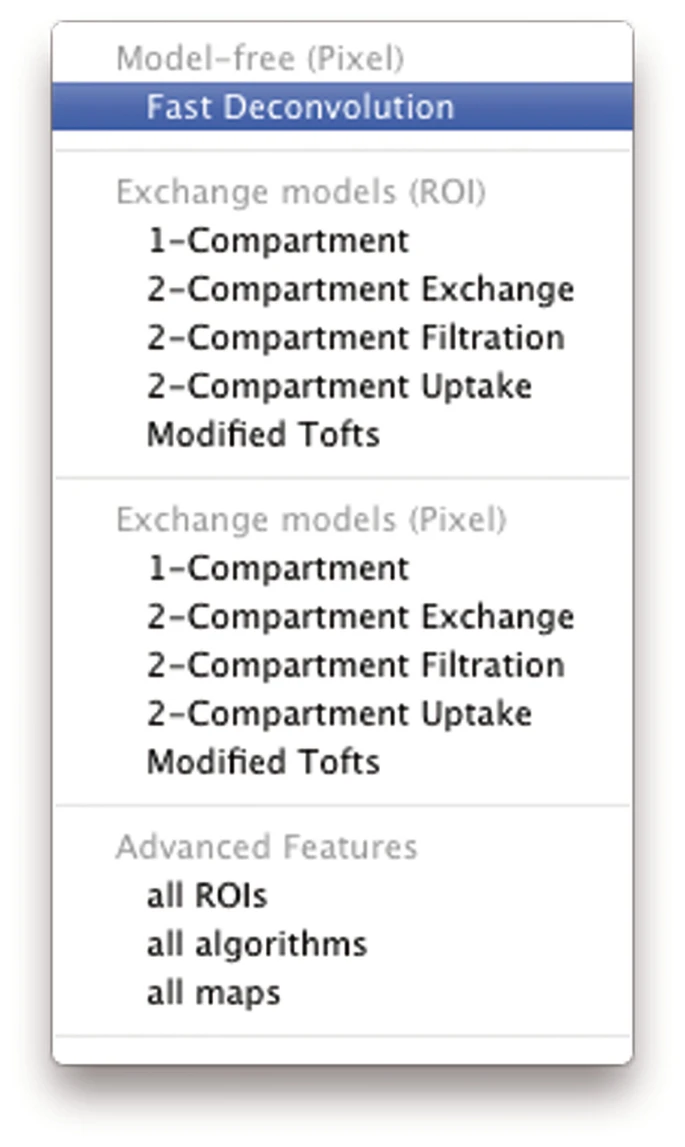

- Select algorithm from the tool bar